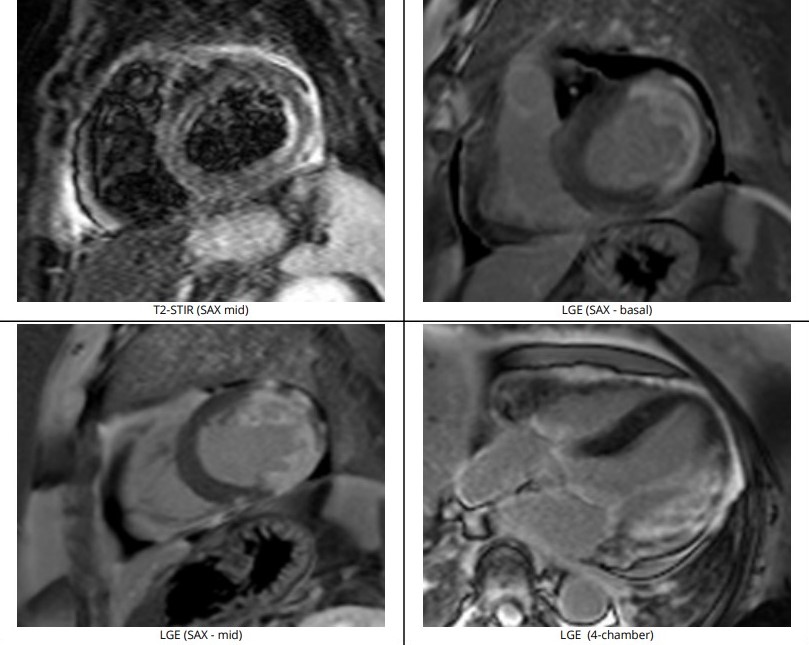

Using guide EBU 3.0/6Fr, RTF crossed lesion OM and predilated with SC 2.0/12mm 8-12atm, then Scoreflex 2.5/15mm upto 20atm. DCB (distal LCx) with Agent 2.5/20mm at 8atm then DES (OM) with Synergy 2.5/24mm at 11atm followed by postdilatation using NC 2.75mm at12-20atm. Using guide JR 3.5/6F, coronary wire RTF to distal RCA, sequential predilatation with SC 2.0/12mm at 10-12atm then Wedge 2.5/15mm at 16-18atm. DCB with Pantera Lux 2.5/20mm at 8atm. Final angiogram showed TIMI III Flow, No dissection. Further evaluation with Cardiac MRI showed increased pericardial signal at the mid-apical lateral wall and part of the mid anterior wall on STIR-T2 study. In the late phase of gadolinium study, there is near transmural enhancement of the basal-apical lateral wall, partially extending into the inferior wall. The overall findings are in keeping with ischaemic cardiomyopathy, complicated with pericardial effusion and mild pericardial effusion and inflammation likely related to Dressler¡¯s Syndrome.